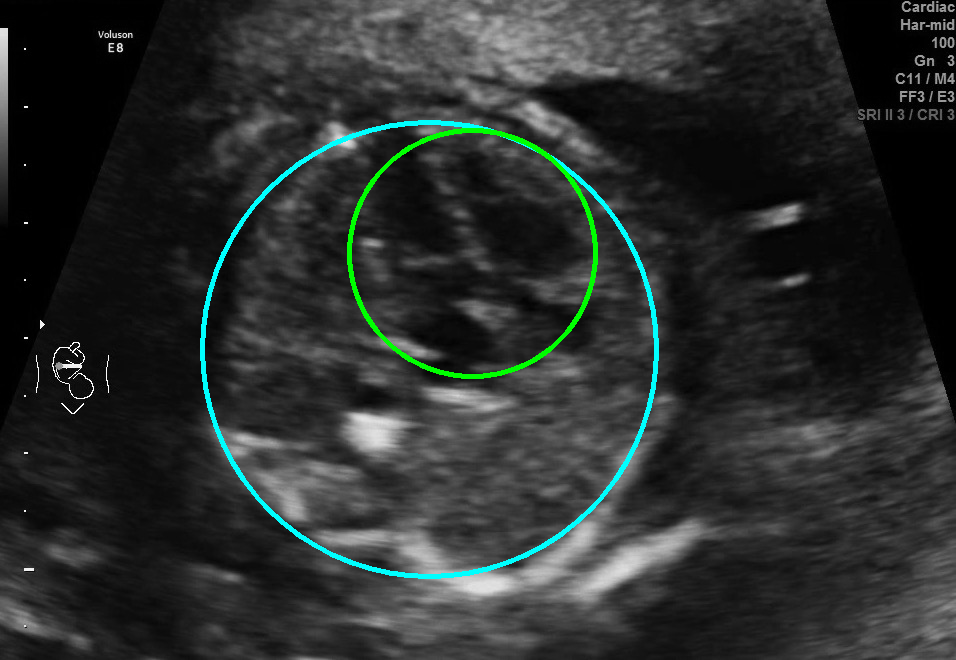

Visualization results of different methods.

Although the segmentation model trained on the fetal ultrasound dataset achieves a relative high average dice scores averaging over 0.9, the fitted ellipse highly depends on the segmentation results. As shown in the middle row of Fig. 2, the segment-based ellipse-fit method performs well when the image quality is good (first row), but the performance degrades when the segmentation is affected by image artifacts such as the acoustic shadowing (second and third row). Our proposed method is more robust to image quality and shadows. We also tried to compare to the GPN [9] with their open source code on our dataset, however, the results are not comparable to ours and those presented in Table. 1. It is difficult to conclude whether it is caused by the network itself or the training strategies. We, therefore, did not include the comparative results in this work.

As shown in Fig. 3 , both the proposed ellipse regression loss and IoU loss are necessary for ellipse detection. If the EllipseNet only supervised by IoU loss (first column), the model fails to optimize the major and minor axis separately, and the predicted ellipses degenerate into circles like the CircleNet. It is clear that the supervision of IoU loss can help to improve the prediction of location and shape (first and second row) and to correct the angle (last row).